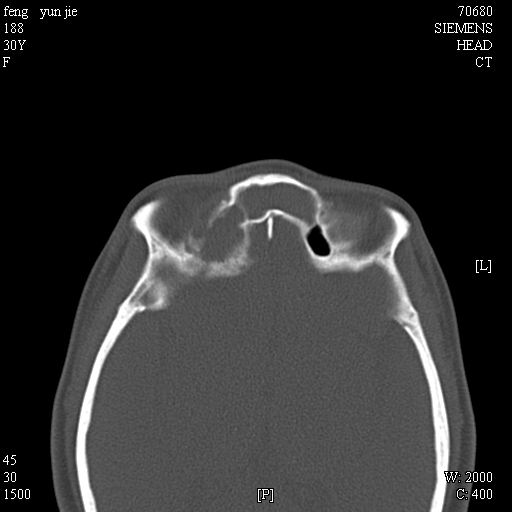

女,37岁,多年前鼻骨骨折过,现在穿刺有炎性分泌物

2、额窦粘液囊肿(右侧水平额窦突入眶内上方)可能性大。

1)左侧鼻骨骨折(陈旧性)。2)双侧额窦及双侧筛窦炎症,伴右侧额筛窦黏液囊肿突入右侧眼眶。

是黏液囊状还是淋巴瘤?建议结合穿刺细胞学检查。